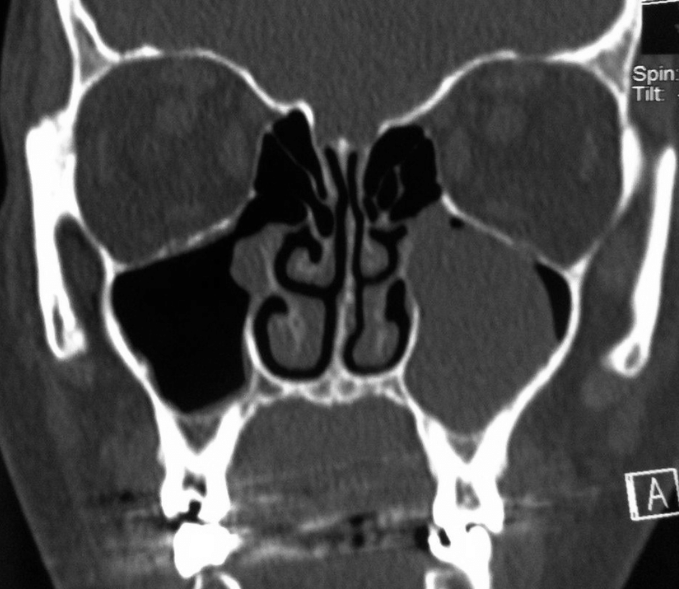

Head & Neck Imaging Course